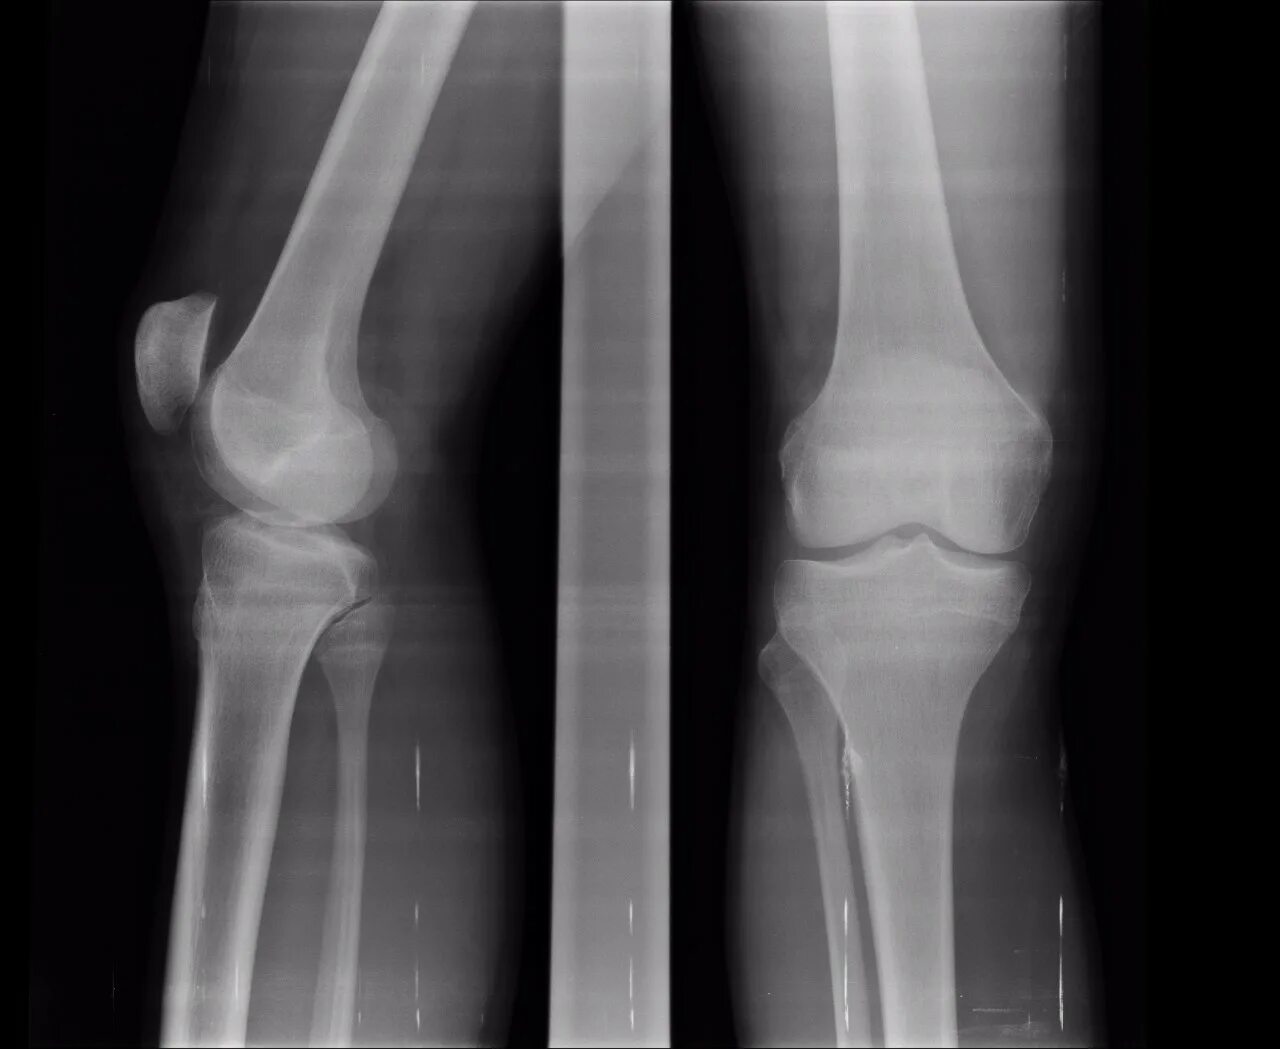

Суставная щель коленного сустава норма